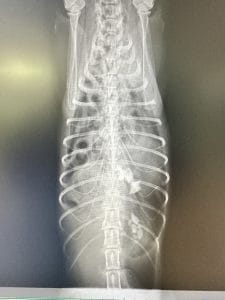

横隔膜ヘルニアは横隔膜に穴が空き、腹腔内の臓器が胸腔へ移動してしまう危険な病気です。今回は事故などで起こる外傷性横隔膜ヘルニアについて、症状・診断・治療の流れを症例をもとに解説します。